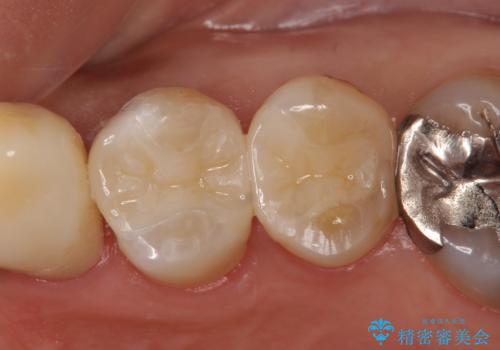

- 右上5番目の歯の被せ物が取れてしまったので治療したいといらっしゃった方の症例です。

虫歯がないことを確認後、セラミックインレーによる修復を行いました。

右上6番目の歯は根尖病変を認めたため、治療を勧めましたが希望されませんでした。

当院のセラミックインレーはemaxという強度と審美性に優れた材料を使用しています。

またプレス方式でインレーを製作しているため、削り出しで製作するCADCAMより優れた適合性も持ち合わせており、虫歯が再発しにくい修復物です。